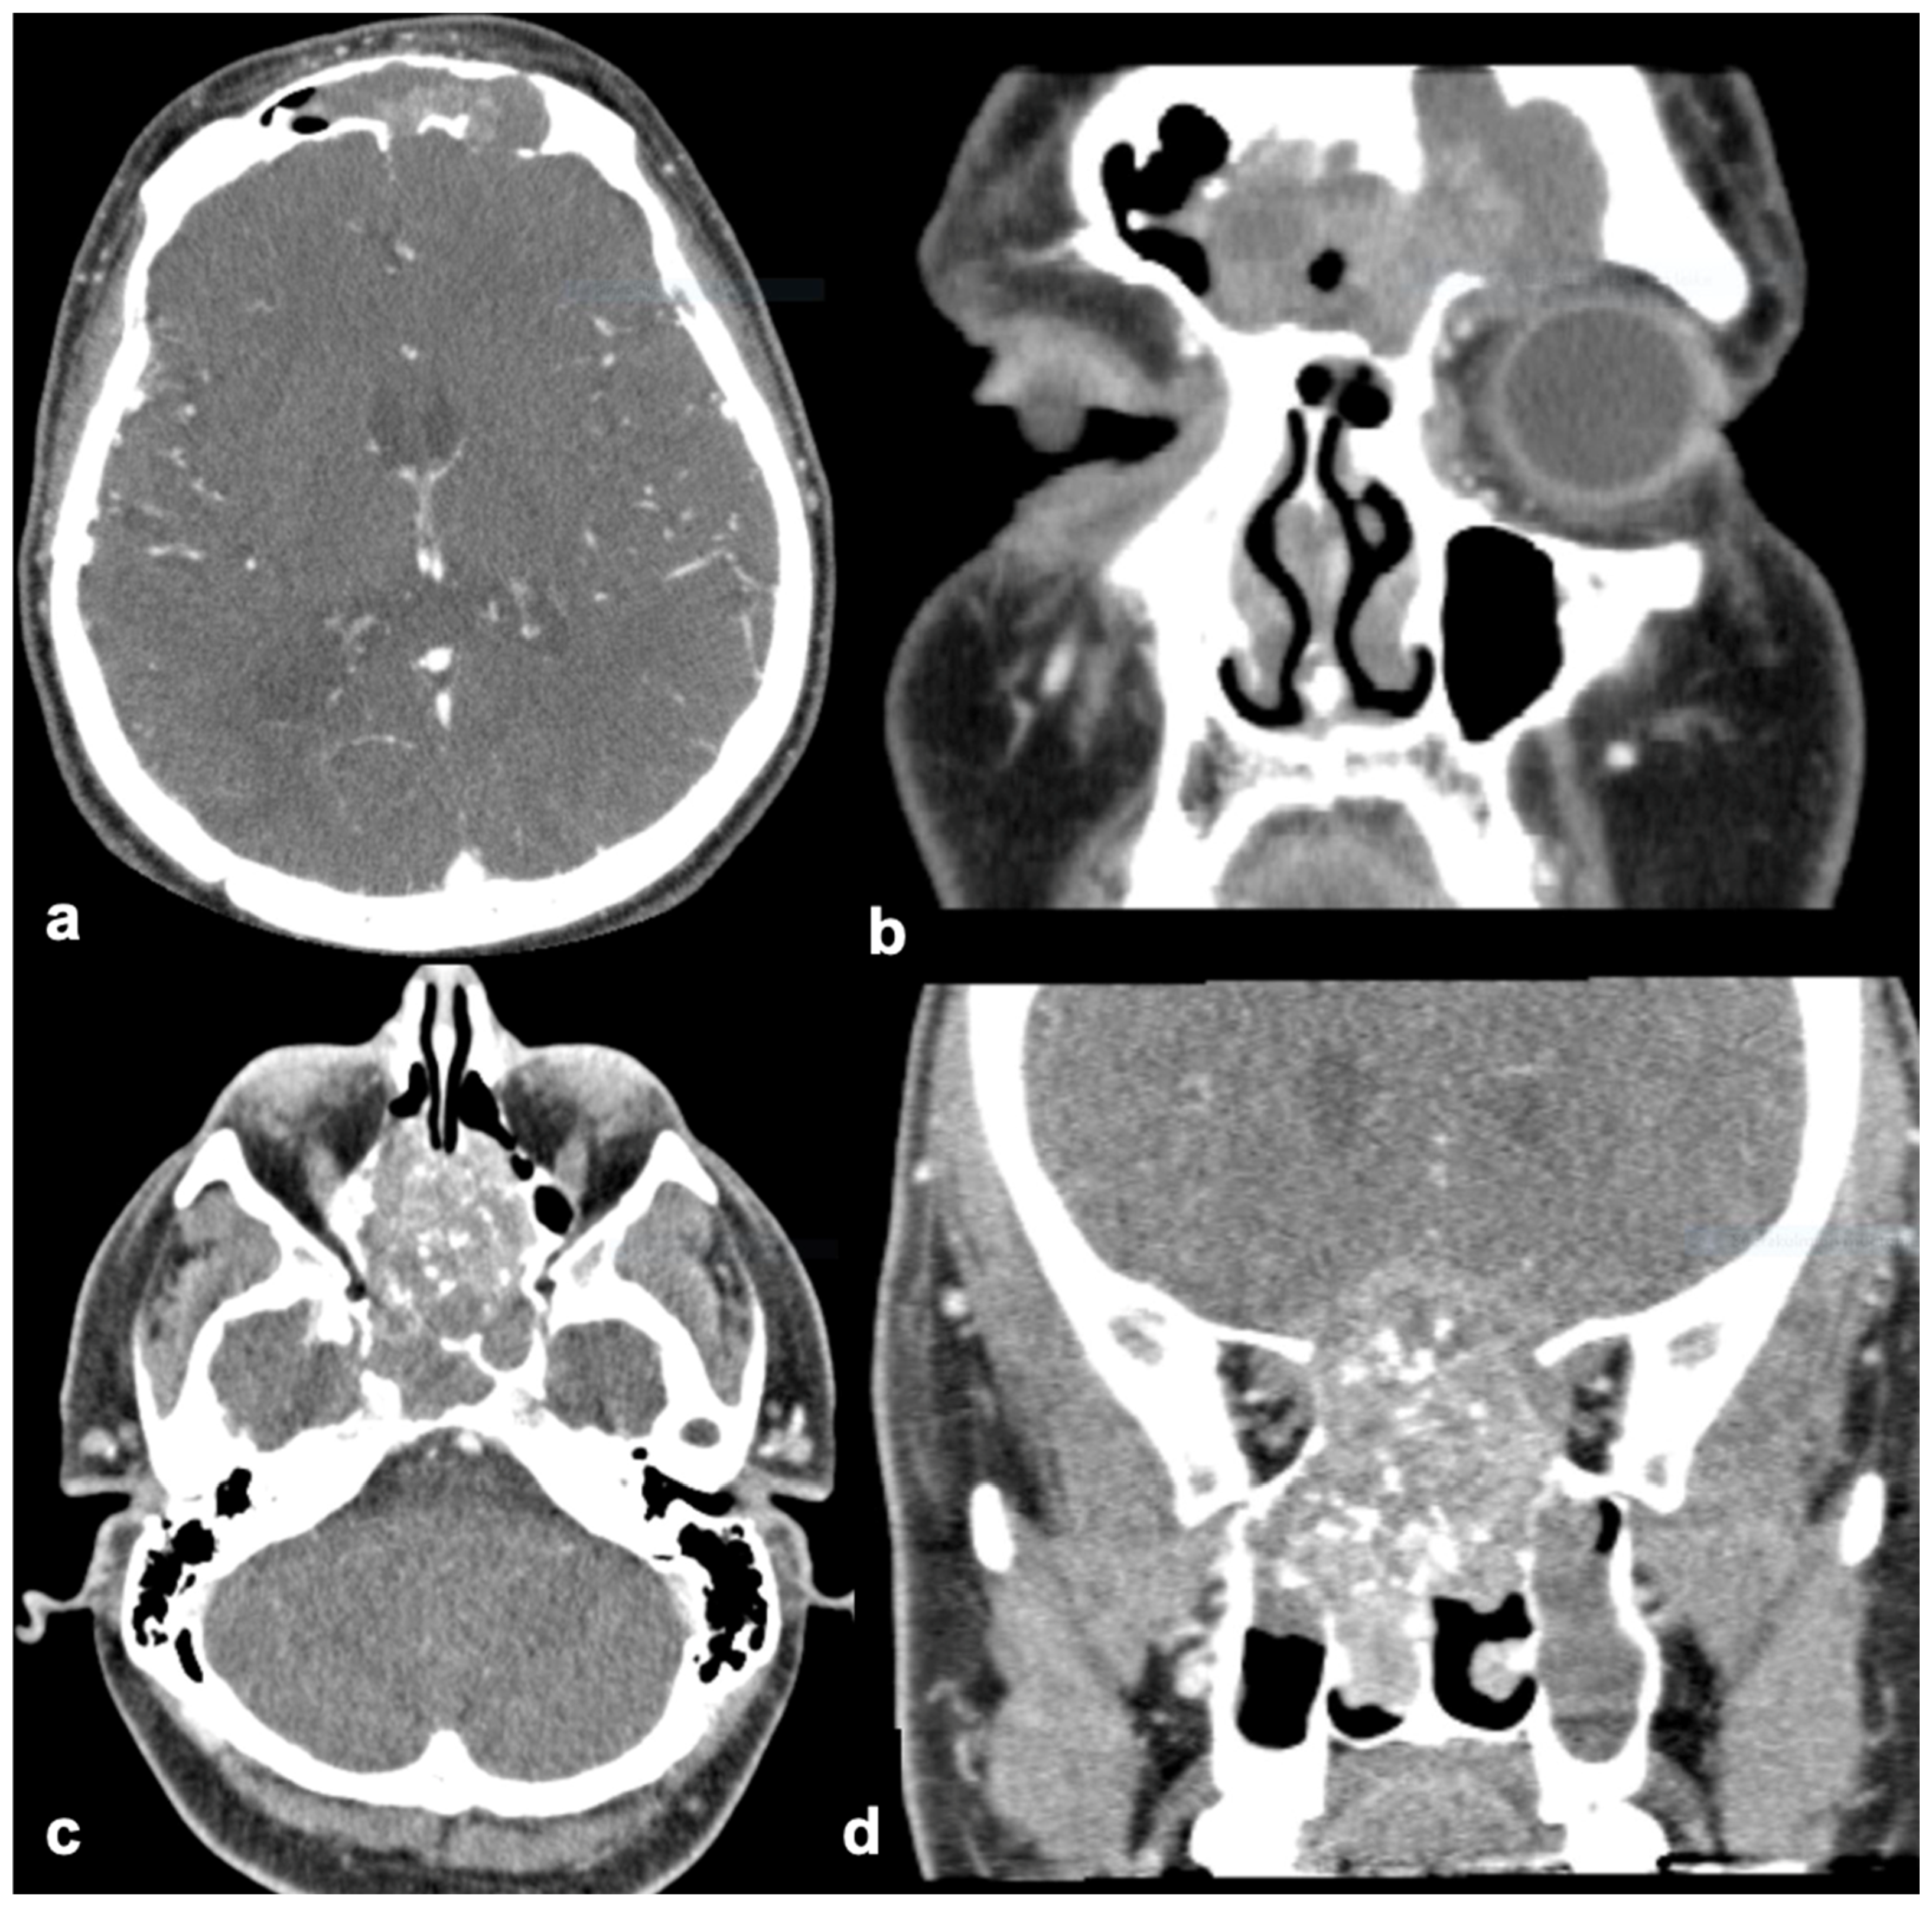

| Findings Only Found in SNIP-SCC | SNIP-SCC n (8) | SNIP n (8) |

|---|---|---|

| Orbit invasion | 12.5% (1) | 0% |

| Intracranial invasion | 25% (2) | 0% |

| Bone defect | ||

| Nasal cavity wall | 50% (4) | 0% |

| Maxillary | 50% (4) | 0% |

| Ethmoid | 25% (2) | 0% |

| Sphenoid | 12.5% (1) | 0% |

| Frontal | 25% (2) | 0% |

| Some differences between groups | SNIP-SCC n (8) | SNIP n (8) |

| Shape of tumor | ||

| Polypoid | 50% (4) | 75% (6) |

| Unsharp | 50% (4) | 25% (2) |

| Tumor location | ||

| Unilateral | 50% (4) | 87.5% (7) |

| Bilateral | 50% (4) | 12.5% (1) |

| Nasal cavity wall | 100% (8) | 100% (8) |

| Maxillary | 50% (4) | 62.5% (5) |

| Ethmoid | 87.5% (7) | 75% (6) |

| Sphenoid | 25% (2) | 0% |

| Frontal | 25% (2) | 37.5% (3) |

| CT enhancement * | 87.5% (7/8) | 62.5% (5/8) * |

| Site of hyperostosis on CT | ||

| Nasal cavity wall | 0% | 25% (2) |

| Maxillary | 12.5% (1) | 0% |

| Ethmoid | 0% | 25% (2) |

| Sphenoid | 0% | 0% |

| Frontal | 12.5% (1) | 0% |

| No differences between groups | SNIP-SCC n (8) | SNIP n (8) |

| Mean diameter of tumor, mm (range) | 57 (30–87) | 48 (20–70) |

| Surface of the tumor | ||

| Smooth | 25% (2) | 12.5% (1) |

| Rough | 75% (6) | 75% (6) |

| Tumor calcification | 25% (2) | 25% (2) |